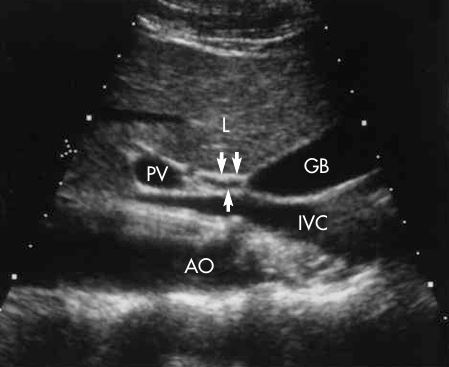

1. Portal Vein

2. Common Bile Duct

3. Gallbladder

SAG - CBD

what plane is this?

transverse

what are the arrows pointing to?

cystic duct